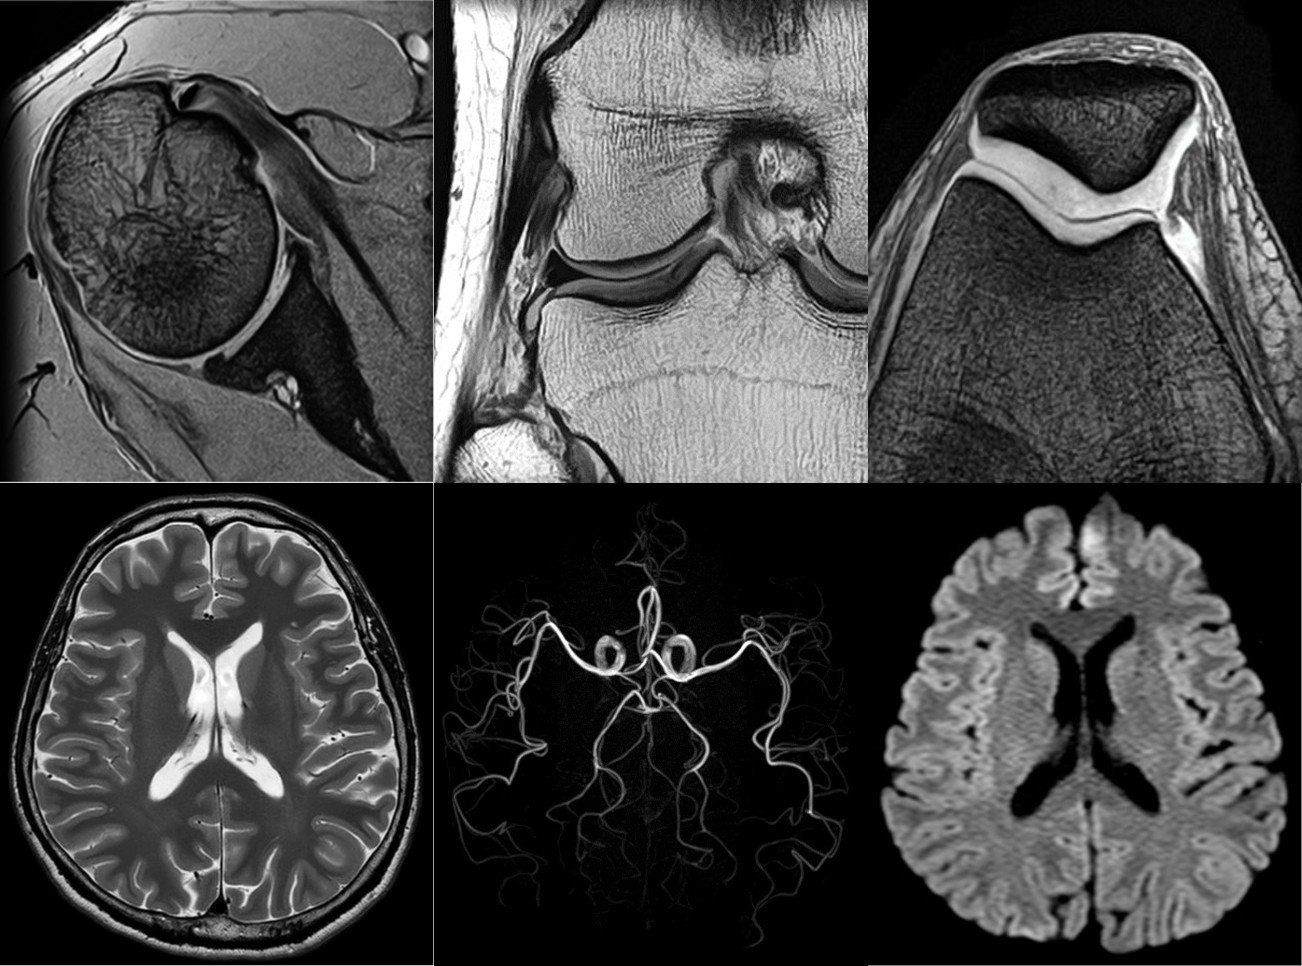

Neueste MRT Technologie von Canon Medical Systems

ORIAN

Der Vantage ORIAN ist ein moderner 1,5 Tesla Premium Magnetresonanztomograph. Es handelt sich um die Erstinstallation in Deutschland mit neuester Technik. Als Referenzzentrum wird dieser hohe Standard fortlaufend aufrecht erhalten.

Der ORIAN erhöht durch seinen großzügigen Patientenzugang von 71 cm erheblich die Patientenfreundlichkeit, ohne Kompromisse bei der Bildqualität einzugehen.

Durch seine leistungsfähigen Gradienten ist er für anspruchsvolle klinische Aufgaben geeignet.

Hervorzuheben ist die Möglichkeit kontrastmittellose Angiographien beispielsweise bei eingeschränkter Nierenfunktion oder allergischer Veranlagung durchführen zu können.